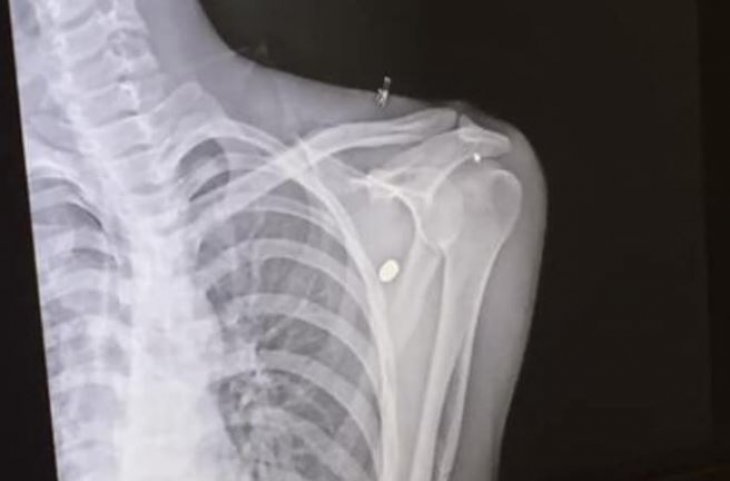

Konya’da kaldırımda yürüyen gencin omzuna mermi isabet etti